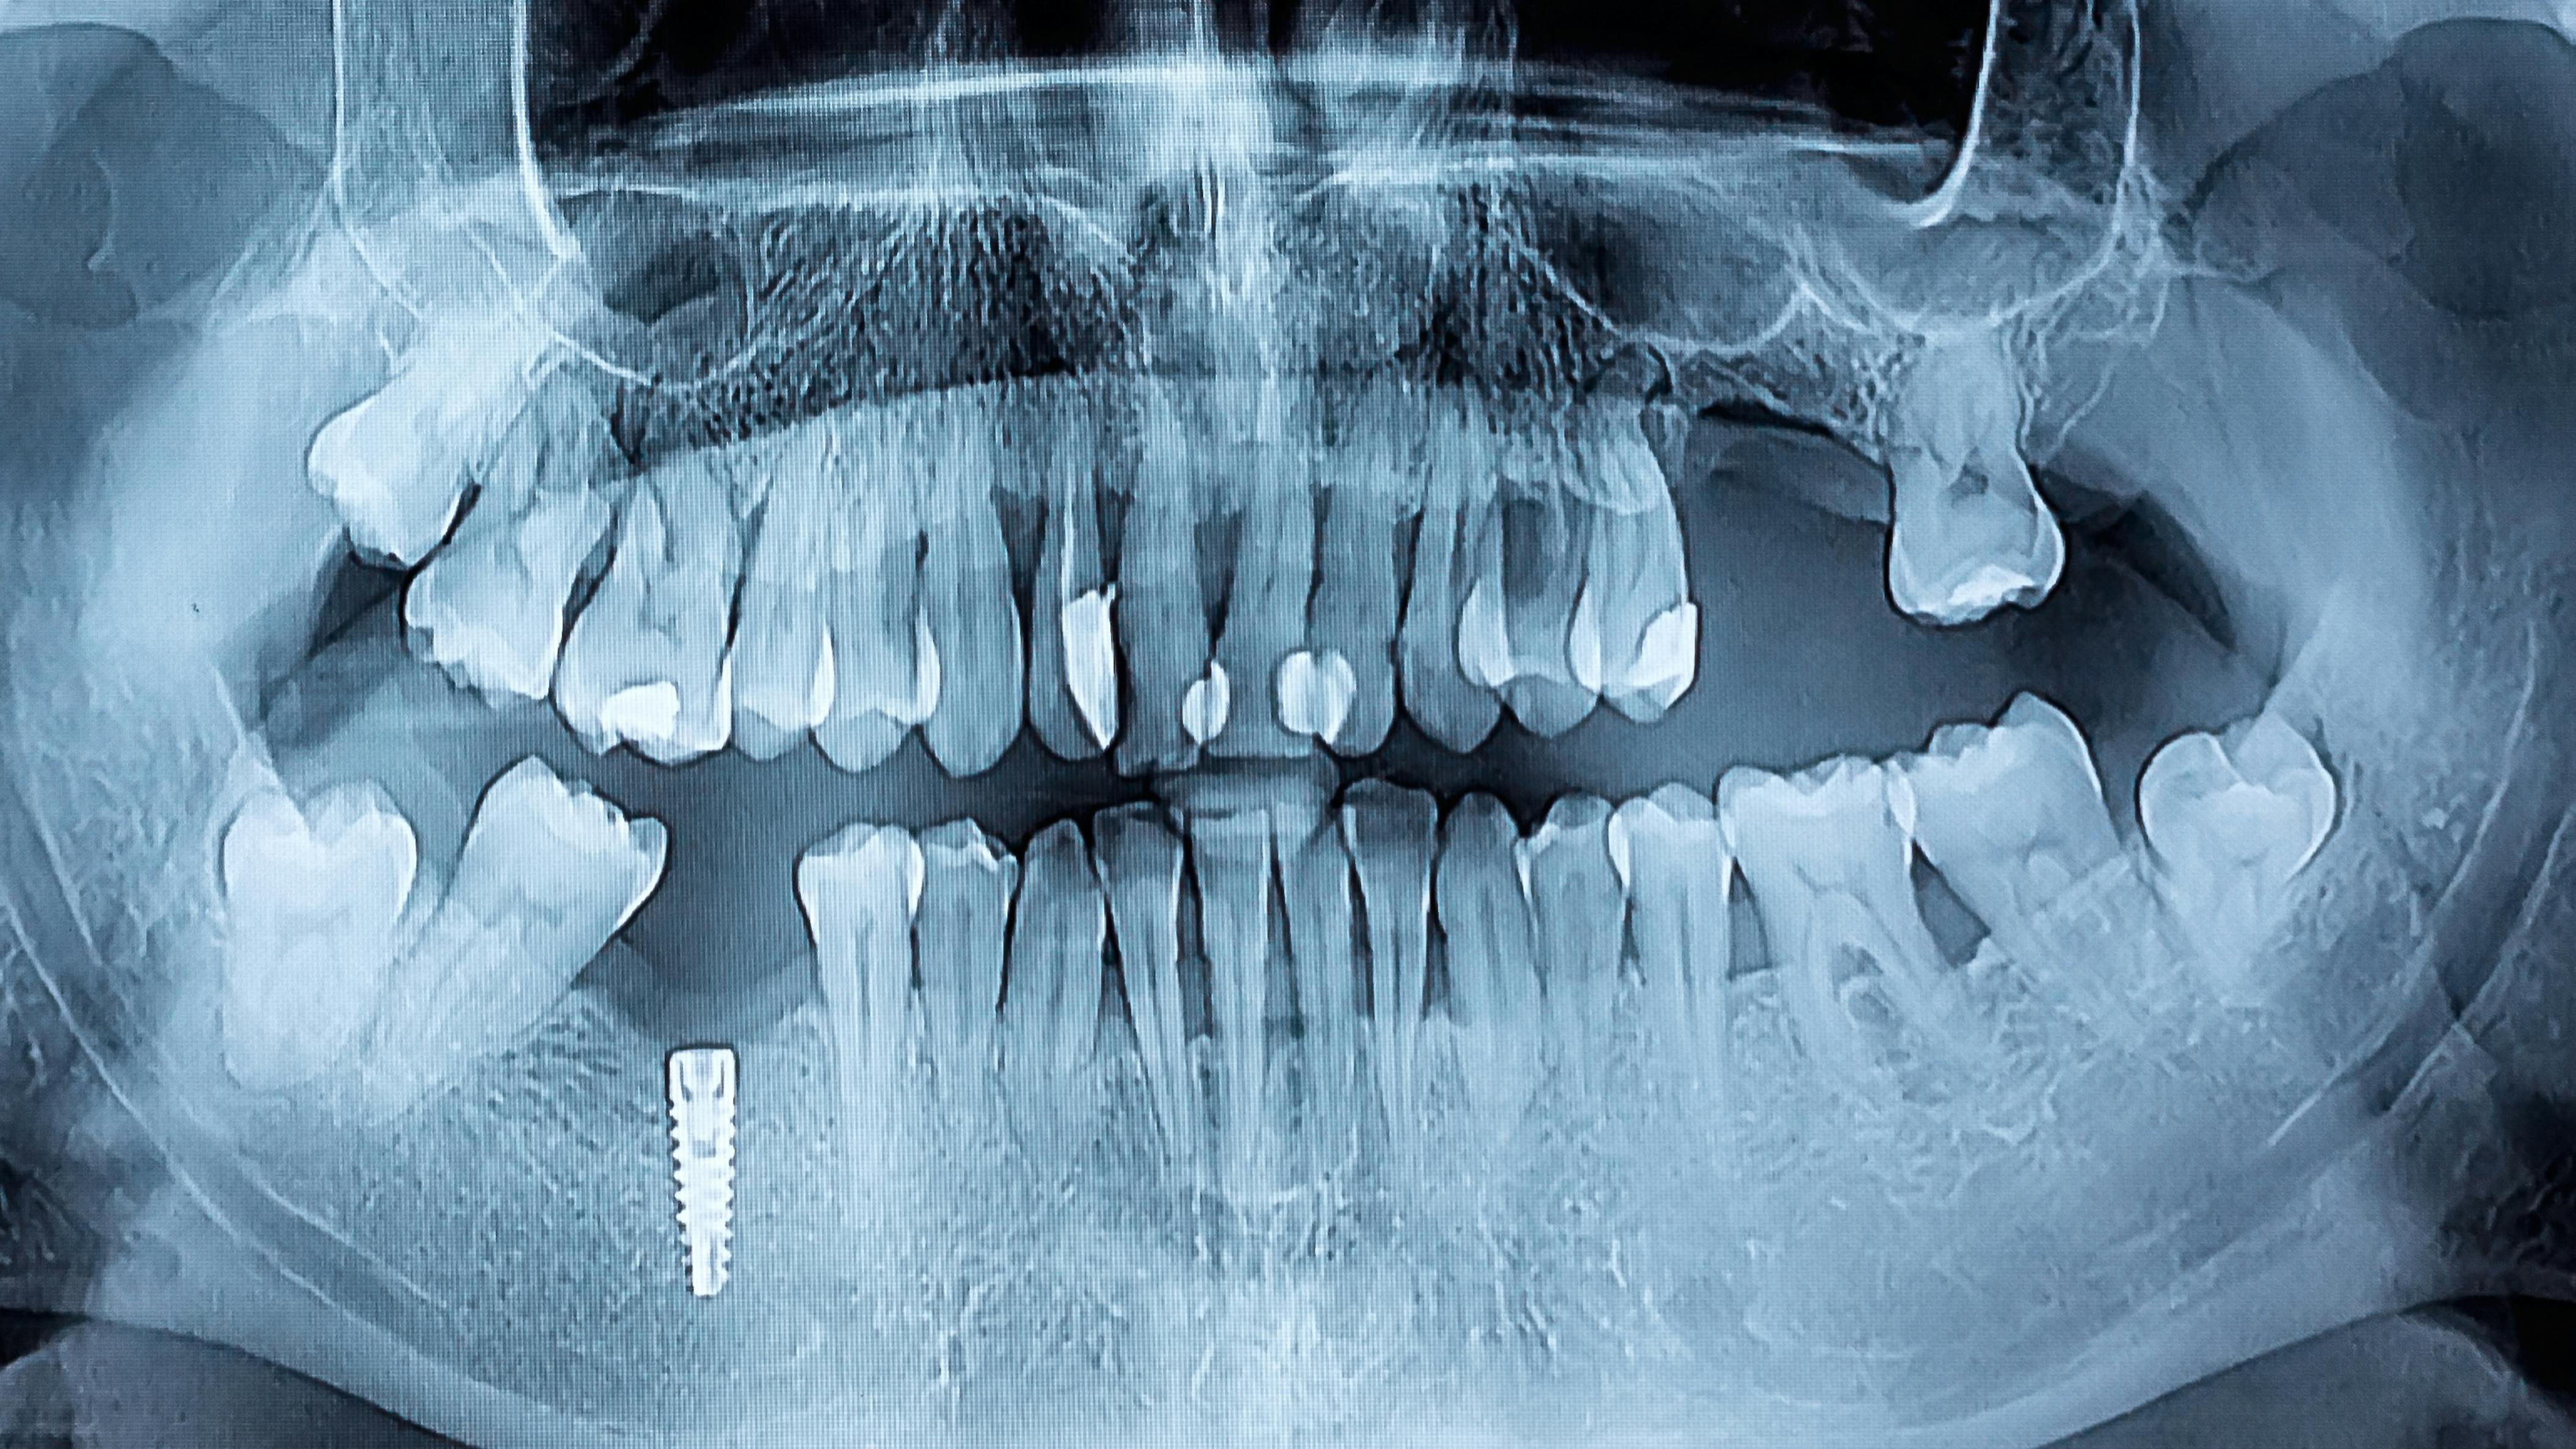

According to Professor Timo Sorsa of the University of Helsinki’s Department of Oral and Maxillofacial Diseases, using the aMMP-8 chairside test can measure and assess active and progressive attachment loss within five minutes, directly in the dentist’s chair and noninvasively. The test complements the diagnostics of periodontitis and peri-implantitis, monitors treatment outcomes, and supports maintenance therapy.6,7

The current oral health treatment protocol could be significantly enhanced by incorporating the developing aMMP-8 rapid test, which can conveniently identify not only periodontitis but also diabetes and its precursors based on oral enzymes. The aMMP-8 enzyme test can also accelerate the diagnosis of gum diseases in patients before dental implant surgery. While traditional methods involve culturing problematic bacteria in laboratories, which takes days to weeks, the aMMP-8 test provides a quicker alternative for identifying issues before implant placement.8